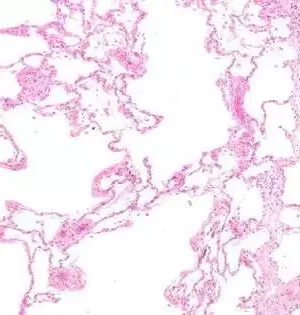

Drug advancement for lung infections is muddled. Most clinical preliminaries that test novel medications flop because research facility models can't precisely repeat human physiology. At present, unambiguous sub-atomic pathways are often demonstrated in exceptionally fake circumstances, utilizing a couple of various cell types in a culture dish in the lab. Such straightforward frameworks don't completely imitate the tissue climate of the lung, and accordingly, these research facility models are inadequate with regards to the portrayal of restoratively pertinent cell correspondence pathways. Upsetting pre-clinical medication improvement: an organotypic model framework for lung researchAnother promising trial model to unthinkingly concentrate on lung